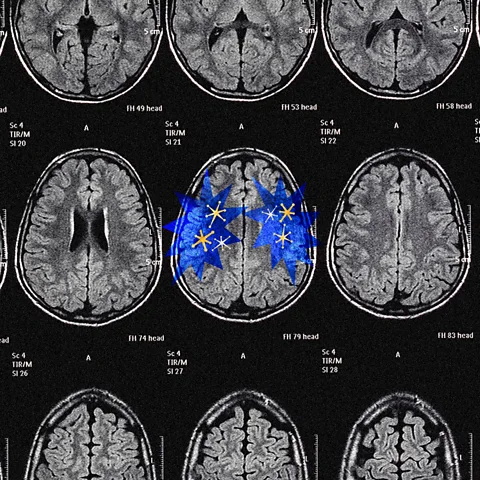

To understand why, we need to look at how two parts of our brain – the cerebral cortex and the reward system, including dopamine – drive us in different directions.

Clearly, the mechanism is incomplete: there must be something that pushes the cortex out of the dark room of nonexperience and into the world of novelty, surprises, goals, and achievements. And there is indeed another module of the brain whose entire essence is to orchestrate precisely such a push. It is called the reward system, and dopamine is the main tool it uses to guide our decisions and motivations, a tool both wonderfully clever and frightfully diabolical. Dopamine is what keeps us moving forward.